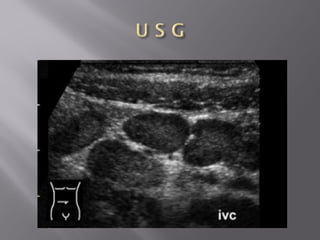

 Portal venousair usually associated with bowel necrosis -noted within 2 cm of the liver capsule  Air is peripheral rather than central  Numerous branching structures